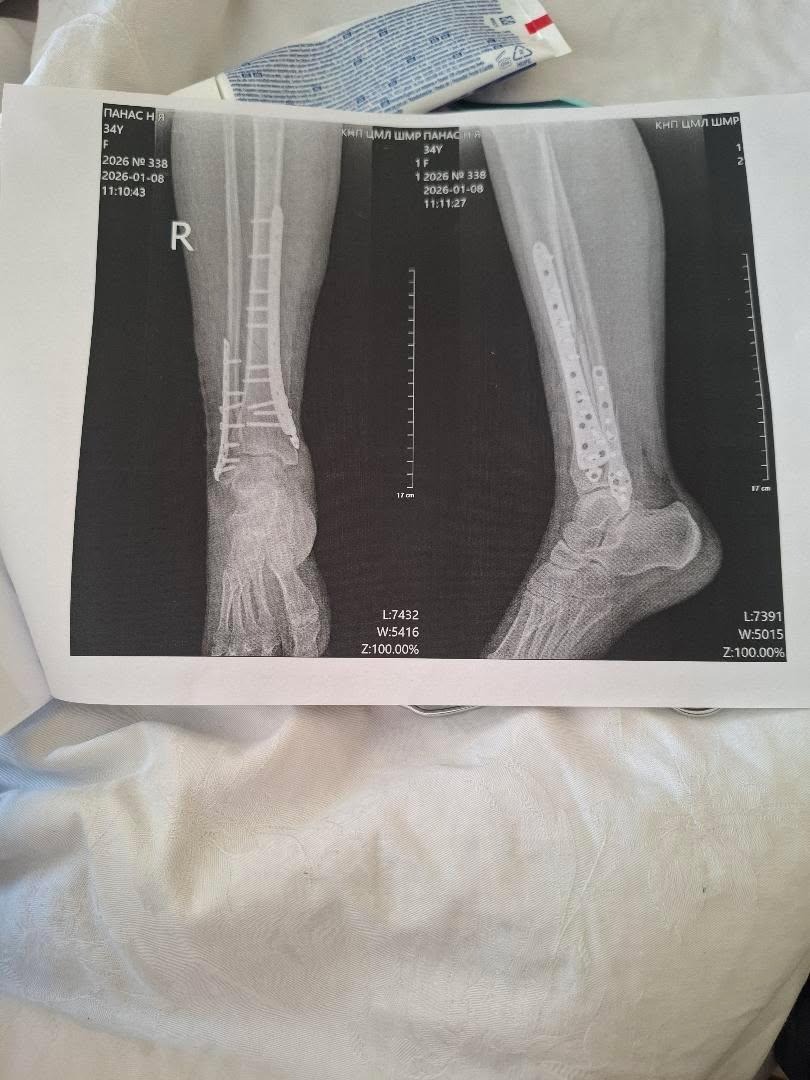

The sad part is, I was trying to get her out of danger. So she wouldn’t be hurt, or worse. On January 2nd, while walking her dog, she slipped on the ice and broke her lower leg. Both Tibia and Fibula.She went through an emergency surgery to immobilize her leg and eventually had plates put in to stabilize the bones. I am not sure if you are familiar with the Ukrainian healthcare system, but she went through all of this without pain medication. With my medical background, I was asking what medications she was taking. She told me benadryl for sleep and an NSAID for pain. All of which she had to pay for out of pocket.

The surgery and hospital stay would have cost over $40,000 here in the United States. But, she informed me it is about $2,000 for her in Ukraine. After 3 weeks in a hospital bed, Nataliia was finally discharged from the hospital, without a cast, wheelchair, crutches, or medication. She was told to stay off of it for 3 months and showed how to bandage the surgical wounds. I am not sure when she will be able to work.